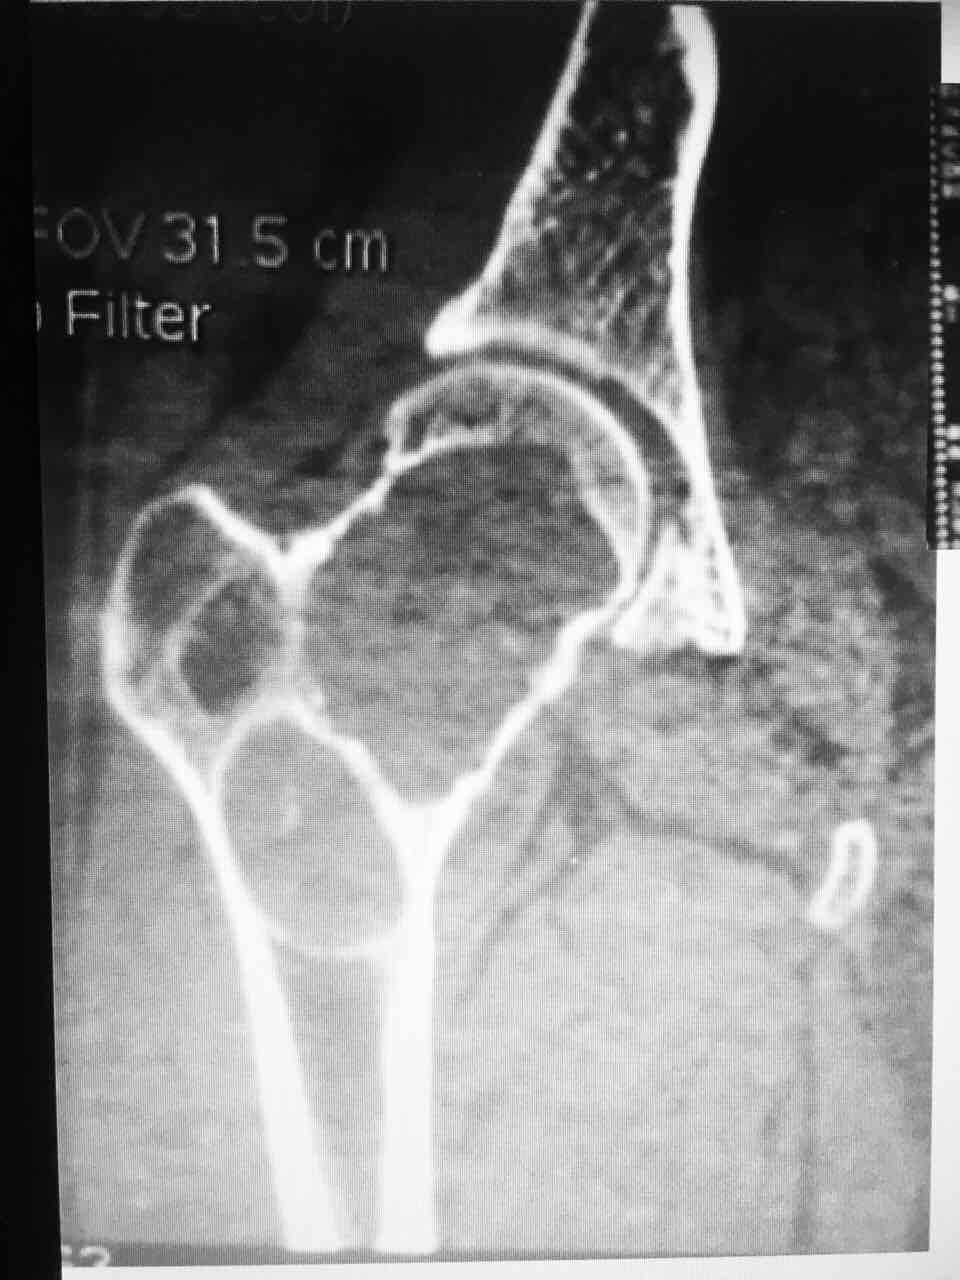

昨天门诊,一青年女性患者,左髋关节疼痛1年,自诉幼时曾行左髋关节手术(具体不详),简单问完病史开始查体,髋关节最常用的查体是 "4"字试验(患者仰卧,一侧下肢伸直,另侧下肢以"4" 字形状放在伸直下肢近膝关节处,并一手按住膝关节,另一手按压对侧髂嵴上,两手同时下压。下压时出现疼痛或者曲侧膝关节不能触及床面为阳性)

敲黑板:问病史的时候,患者诉左髋关节做过手术,虽然不知道什么手术,但是做"4" 字试验要轻柔或者让患者自己完成,如果强行去做很容易出问题。开骨盆正位片,等待结果。

结果回报大吃一惊,左侧股骨颈肿瘤,大部分骨质被吃没了,就剩下一层菲薄的皮质,如果刚刚做"4" 字试验,用力下压,99%要压骨折了。